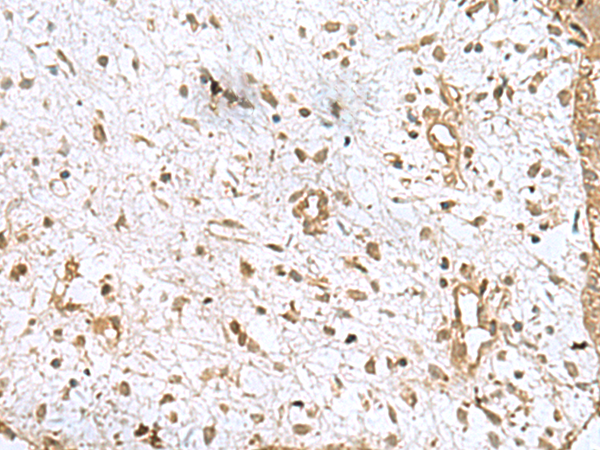

分类: 科研抗体货号: P03325别名: PKDR1; SAMD6; NPHP16; ANKRD14应用: IHC反应种属: Human, Mouse, Rat